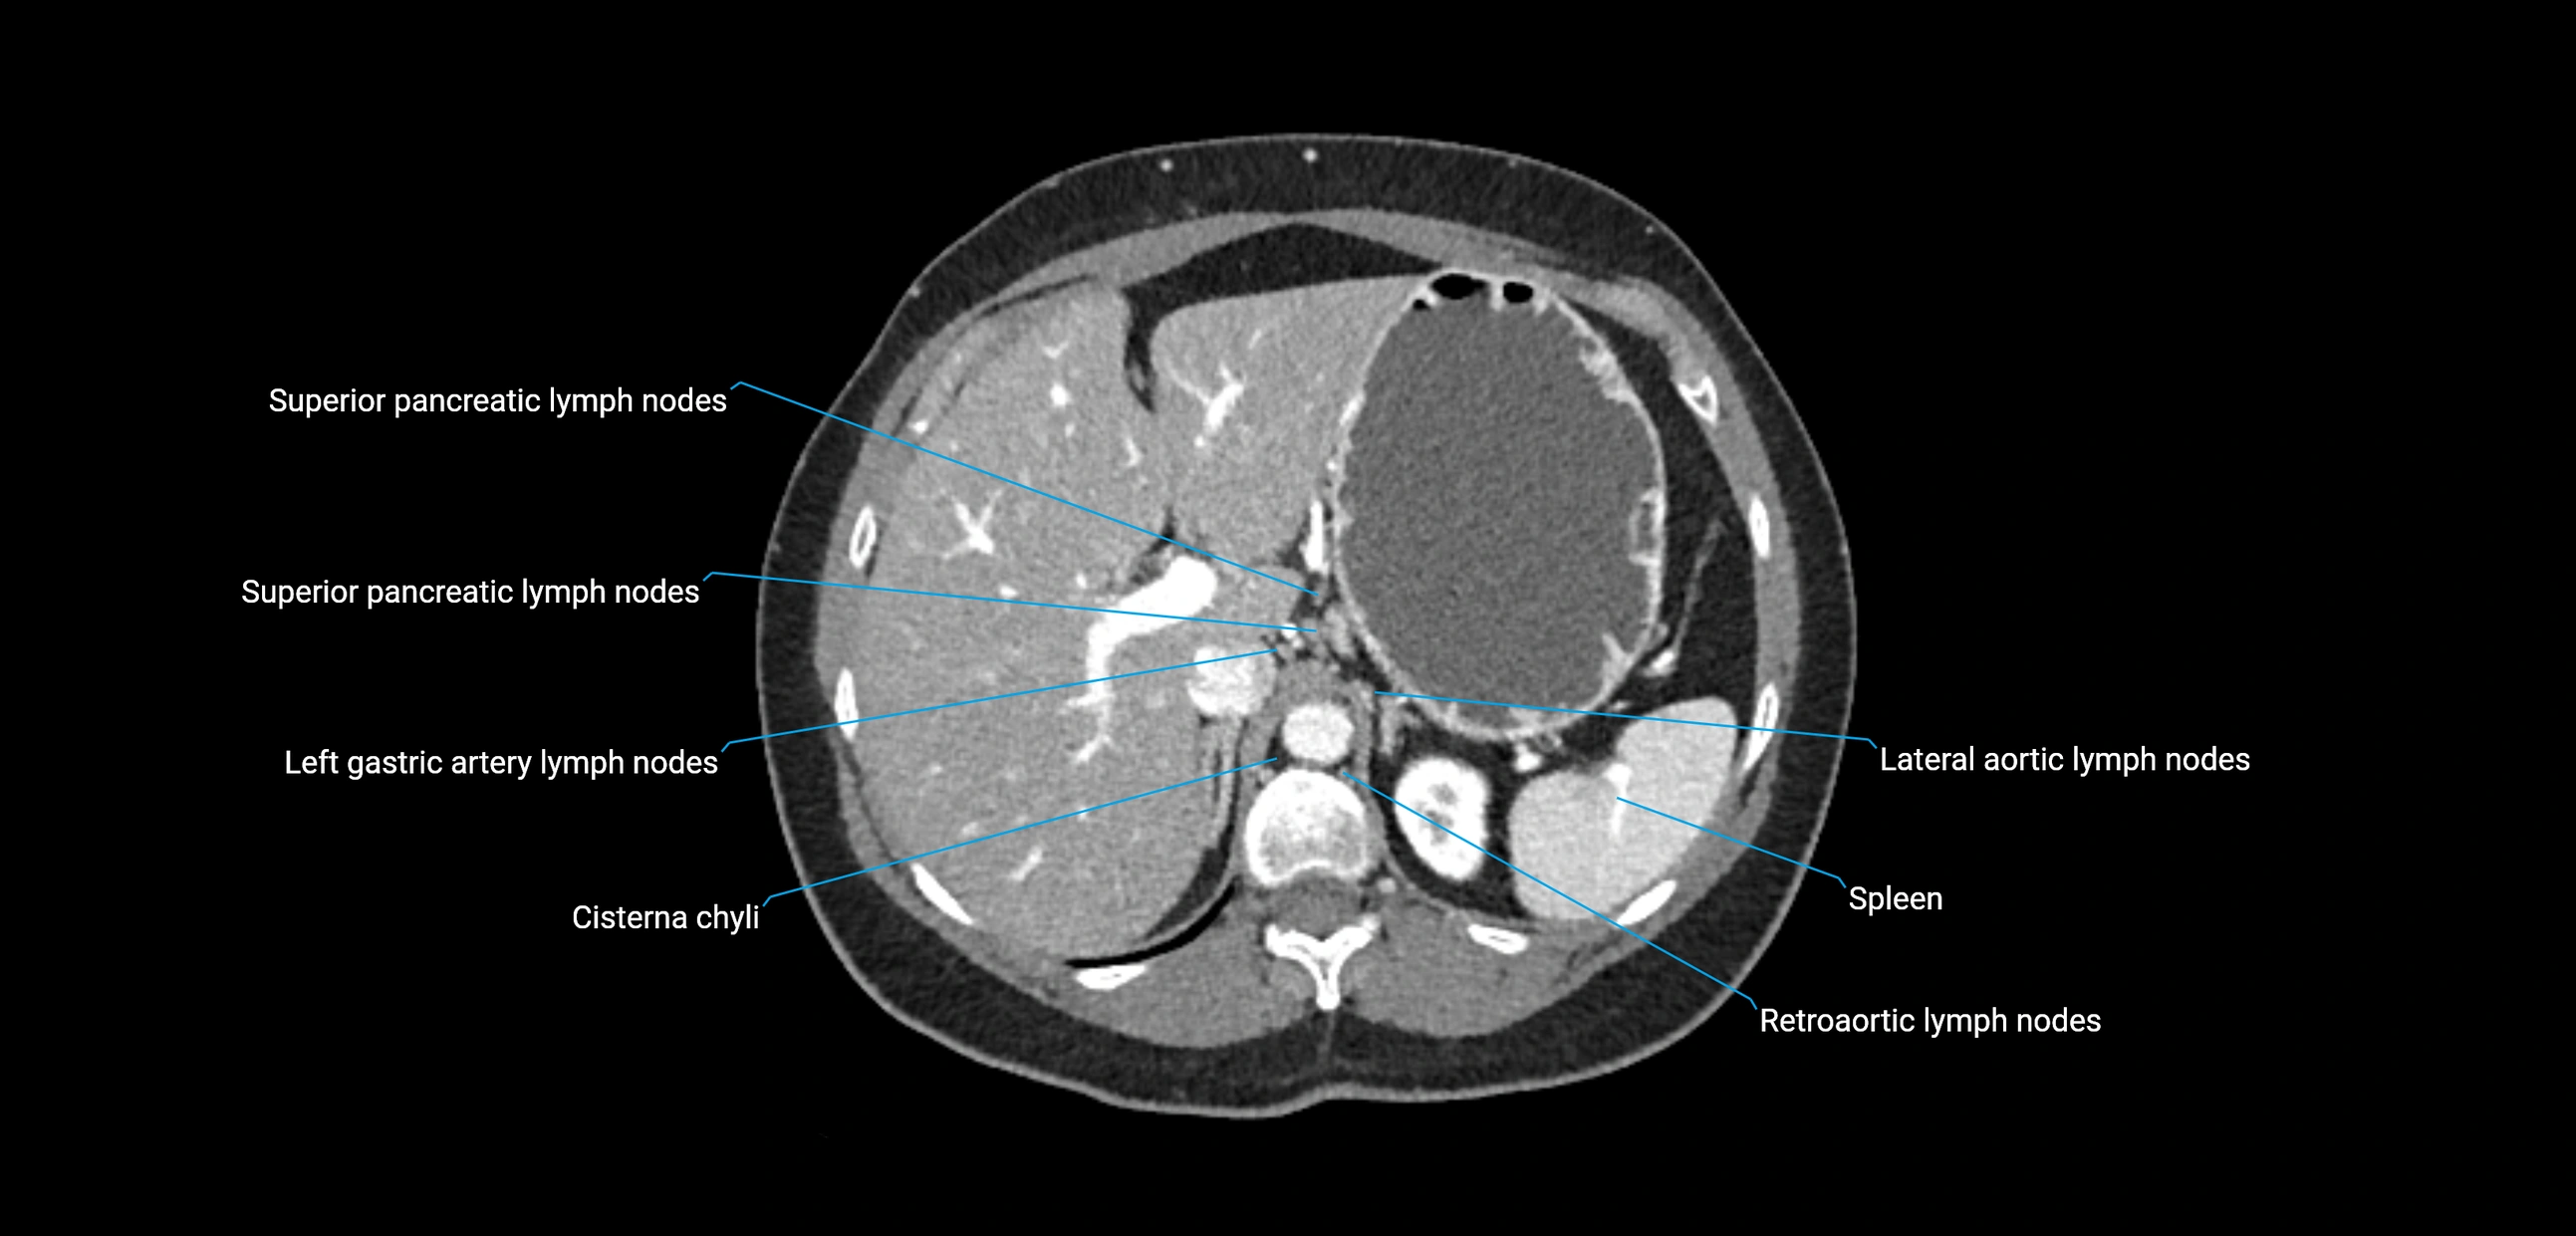

The lateral aortic lymph nodes (also called para-aortic lymph nodes) are a major group of retroperitoneal lymph nodes located along the abdominal aorta and its branches. They lie between the diaphragmatic crura superiorly and the bifurcation of the aorta at L4 inferiorly.

They are positioned on both sides of the abdominal aorta:

• Right lateral aortic nodes: adjacent to the inferior vena cava (IVC)

• Left lateral aortic nodes: lateral to the abdominal aorta

These nodes receive lymph from a wide range of abdominal and pelvic structures. Specifically, they drain lymph from the kidneys, suprarenal glands, gonads (testes/ovaries), uterus, uterine tubes, and pelvic organs, before converging into the lumbar lymphatic trunks, which terminate in the cisterna chyli → thoracic duct.

CT image

image